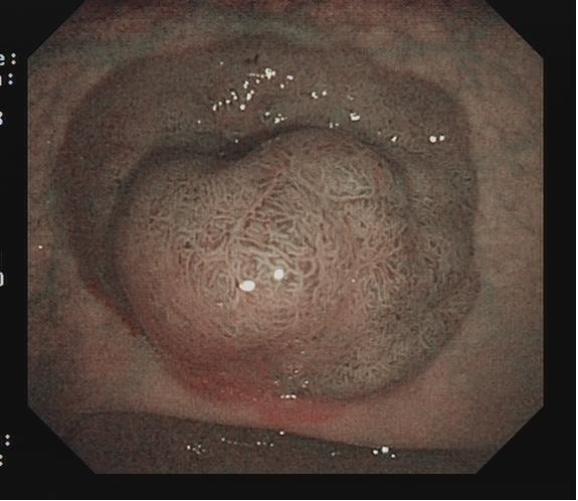

对于大型Ⅰp病变,除以上注意事项外,应采用热圈套方式切除,切除前应于蒂根部充分黏膜下注射(经内镜注射针将2~10 mLl万单位的肾上腺素+亚甲蓝+生理盐水混合液注射于黏膜下,边退针边注射),致使蒂部充分隆起,易于切除(图 3),切除过程中病变应避免接触肠壁,以免形成闭合回路,灼伤肠壁。

图3 Ⅰp 型病变EMR治疗示意图

需要注意的是大型Ⅰp型息肉若蒂部较粗,则可能含粗大滋养血管,切除后极易出血。切除过程中可采用凝-切-凝的方式,减少出血风险。部分较大息肉,可采取分块切除方式,降低操作难度,但此法不利于病理评估。